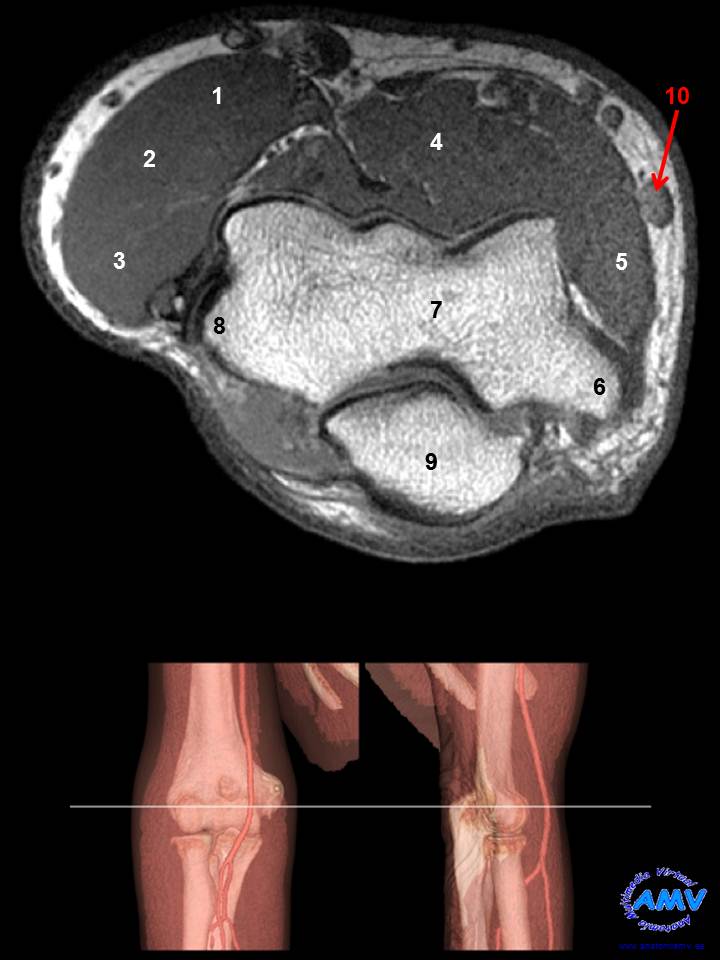

RMN Axial de Codo

ms_rmn_05.jpgIndique que estructura se señala con el número correspondiente:

El nº 1 señala al músculo .

El nº 2 señala al músculo .

El nº 3 señala al músculo .

El nº 4 señala al músculo .

El nº 5 señala al músculo .

El nº 6 señala a la estructura ósea .

El nº 7 señala a la estructura ósea .

El nº 8 señala a la estructura ósea .

El nº 9 señala a la estructura ósea .

El nº 10 señala a la vena .